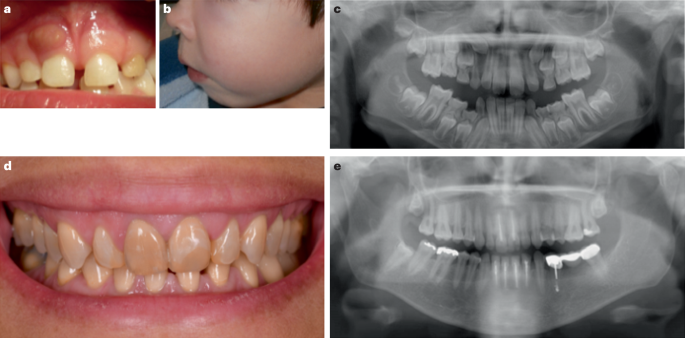

X-linked hypophosphataemia (XLH) is a rare metabolic bone disorder caused by pathogenic variants in the PHEX (phosphate-regulating endopeptidase homologue X-linked) gene, which is mainly expressed in bone (osteoblasts and osteocytes) and teeth (odontoblasts and cementoblasts). The incidence of XLH is 3.9 per 100,000 live births and the prevalence ranges from 1.7 to 4.8 per 100,000 people1,2,3. The pathogenesis of XLH is complex and incompletely understood. Many features of the disease can be explained by increased secretion of the phosphaturic hormone fibroblast growth factor 23 (FGF23) from bone. Binding of FGF23 to the FGF receptor 1–alpha-Klotho co-receptor complex results in downregulation of the sodium-dependent phosphate transporters NPT2a (encoded by SLC34A1) and NPT2c (encoded by SLC34A3), a decrease in 1,25-dihydroxyvitamin D (1,25(OH)2D) synthesis and an increase in 1,25(OH)2D degradation in the proximal renal tubules, ultimately causing hypophosphataemia and hypovitaminosis D4. The clinical consequences of XLH can include rickets, osteomalacia, bone pain, leg deformities (Fig. 1), premature fusion of the cranial sutures and disproportionate short stature that usually develops during the first 2 years of life5. Patients also show hypomineralization of teeth and are prone to tooth abscesses and periodontitis6 (Fig. 2). Adult patients with XLH may show pseudofractures due to osteomalacia as well as osteoarthritis, enthesopathies, spinal stenosis, hearing loss, depression and reduced quality of life7. The pathogenesis of osteoarthritis and enthesopathies and to what extent these are sequelae of certain primary manifestations of XLH is poorly understood8,9.

a, Oral clinical view of a 5-year-old male patient with X-linked hypophosphataemia (XLH) showing a spontaneous dental abscess on the right upper temporary central incisor. The tooth shows no discoloration or carious lesion and the child and his mother reported no history of trauma. b, Maxillo-facial cellulitis due to spontaneous necrosis of the left upper temporary canine in the same patient at the age of 7 years. c, Panoramic radiograph of the same patient at the age of 8 years showing mixed dentition with characteristic dental features of XLH, including a normal (slightly thin) enamel layer, a radiolucent dentin layer with enlarged pulp chambers and prominent pulp horns on both temporary and permanent teeth. d, Oral clinical view of a 49-year-old woman with XLH who was diagnosed at the age of 4 years. The patient was treated with oral phosphate supplements and active vitamin D during growth for 12 years before the treatment was stopped at the age of 16 years. This treatment was resumed for 4 years from the age of 40 years before being replaced with burosumab, which had been taken for 5 years. e, Panoramic radiograph of the same patient showing generalized horizontal alveolar bone loss and teeth treated endodontically owing to dental infections.

The RCT in children with XLH and persistent rickets did not report a beneficial effect of burosumab treatment compared with oral phosphate and active vitamin D on the occurrence of dental abscesses67. Considering the time required for tooth formation, the duration of treatment (64 weeks) may have been too short to show a clinical benefit. Moreover, the dental infections that were reported in this RCT occurred in teeth that had mineralized before the onset of burosumab treatment. Primary teeth mainly form during pregnancy and the early months of life, whereas permanent teeth progressively form from birth onwards80. A post hoc analysis of the RCT reported that young children (aged <5 years) who were treated with burosumab were less susceptible to dental abscesses than those who were treated with oral phosphate and active vitamin D (abscesses in 0% versus 25%, respectively)74. By contrast, among older children (age 5–12 years), dental abscesses were reported in 53% of those treated with burosumab but in none of those treated with oral phosphate and active vitamin D. These findings suggest a window of opportunity during tooth formation for burosumab treatment to limit the risk of dental abscesses.

A prospective case–control study in 10 children with XLH aged 8.8 ± 3.8 years at initiation of burosumab therapy showed persistence of enlarged pulp chambers, a hallmark feature of XLH, in the permanent mandibular molar after 3 years of this treatment81. However, only one patient had recurrent abscesses involving a deciduous molar tooth during the 3-year follow-up period. A monocentric retrospective study that included 71 children with XLH (38 on oral phosphate and active vitamin D (mean age 2.92 ± 3.0 years at XLH treatment onset) and 33 on burosumab therapy (mean age 8.36 ± 3.81 years at XLH treatment onset)) showed that burosumab therapy for an average of 3.2 years was associated with a significant decrease in the number of dental abscesses compared with oral phosphate and active vitamin D; burosumab treatment was associated with 0.01 ± 0.03 abscesses per month of follow-up whereas treatment with oral phosphate and active vitamin D was associated with 0.04 ± 0.05 abscesses per month of follow-up (P = 0.04)82. None of these studies reported an impact of treatment on the occurrence of dental caries or maxillofacial cellulitis. Thus, in young children, burosumab might have a small beneficial effect for the prevention of dental abscesses compared with oral phosphate and active vitamin D. More prospective data are needed to fully assess the potential beneficial effects of burosumab on dental health.